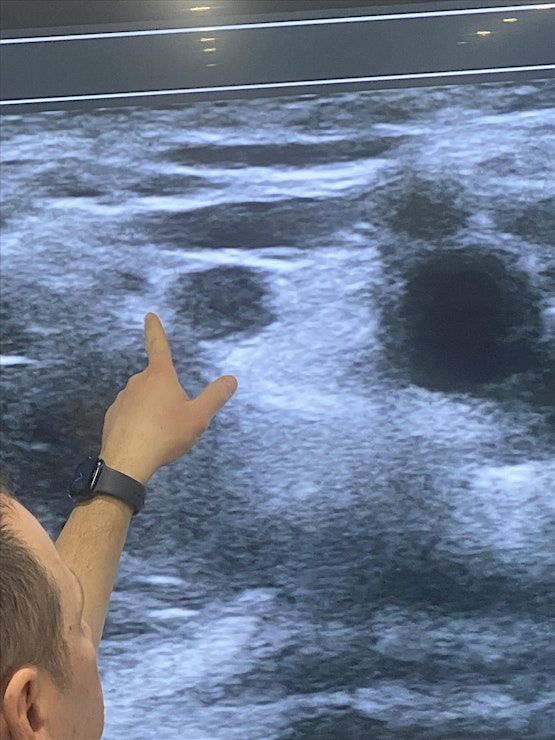

This 1 day intensive workshop has been developed for both novices and advanced pain physicians providers who would like to either learn the basics or further advance their skills in ultrasound guided pain procedures and regional anesthesia. Participants will have up to 6 hours of hands on ultrasound scanning on live models and lecture to learn and identify different sono‐anatomy. At the end of the workshop, you will be expected to have gained thorough knowledge and immense confidence in the use of ultrasound for pain procedures

• Identify normal sono‐anatomy and aberrations

13:00 -15:00 Hands on Scanning: Live Models